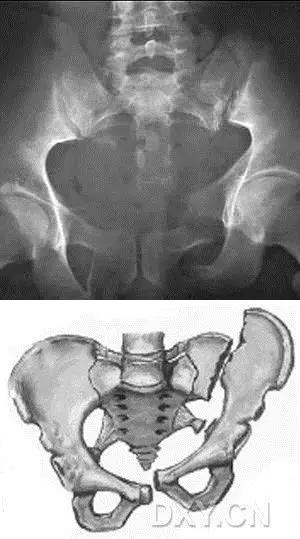

2. Malgaigne 骨折 (bucket handle 骨折,即桶柄骨折)

不稳定性骨盆骨折伴有前方和后方的骨折线累及髋关节。

(来源:radiopaedia)